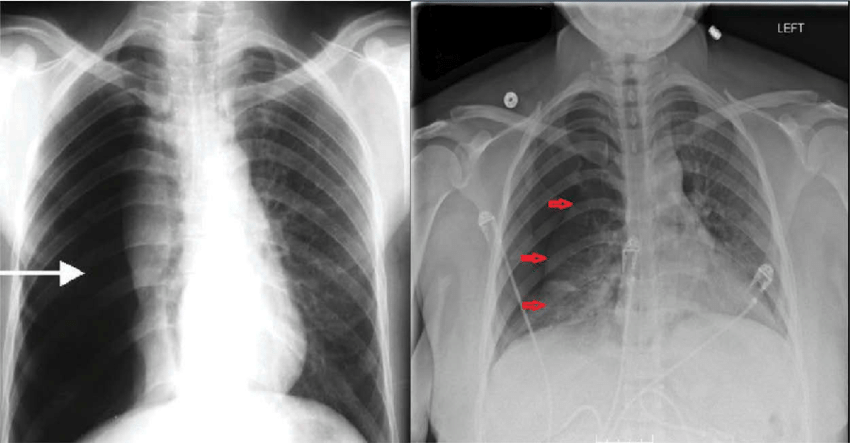

기흉은 흉강 내에 공기가 채워져 폐가 정상적으로 팽창하지 못하는 상태를 말합니다. 이 질환은 생명을 위협할 수 있으므로, 정확한 이해와 적절한 대처가 필요합니다. 오늘은 기흉의 원인, 증상, 자가진단 방법, 치료 옵션에 대해 상세히 알아보겠습니다.

- 정의: 폐 또는 흉강 내에 공기가 채워지는 상태

- 발생 원리: 흉강 내 음압 공간에 공기가 유입되면서 발생

- 흉강 구조: 벽측 흉막과 장측 흉막으로 둘러싸인 공간

- 정상 상태: 흉강 내 소량의 흉수 존재

- 비정상 상태: 공기나 가스 유입으로 인한 기흉 발생